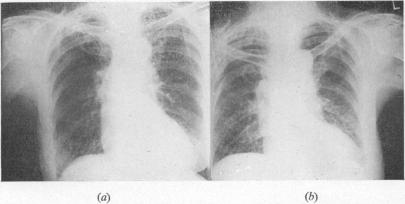

RESPIRATORY DISTURBANCES CAUSED BY GENERAL SURGICAL OPERATIONS.

https://cdn.ncbi.nlm.nih.gov/pmc/blobs/a978/2311602/b8b1fd0cb0ea/annrcse00193-0053-a.jpg